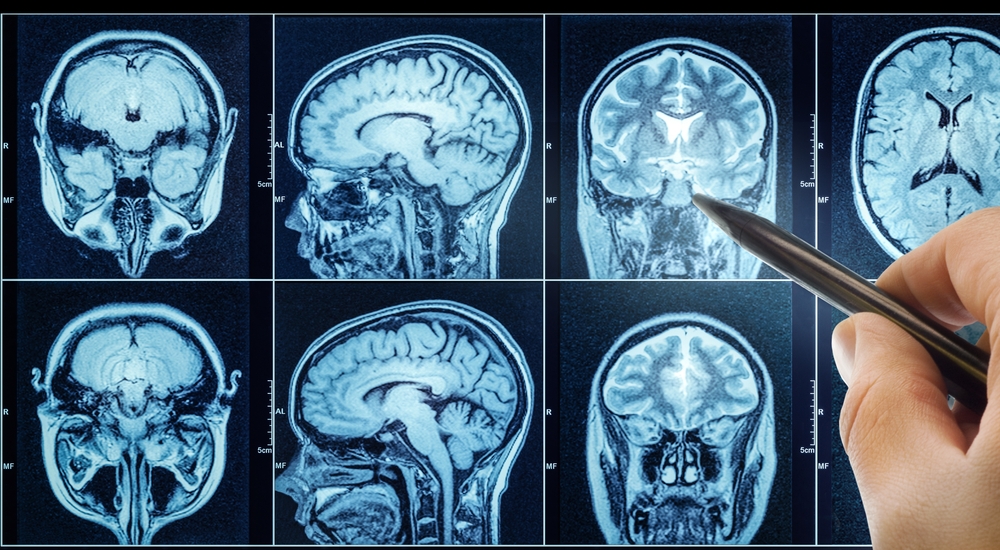

MRI scans revealed dramatic effects in a remarkably short time. The female patient experienced near-complete tumor regression just five days after her infusion. Her MRI showed that the mass had all but disappeared, a result that left researchers stunned. For a cancer known to resist even the strongest treatments, this level of response was unprecedented.

The second patient showed an 18.5% tumor reduction just two days after infusion. By day 69, this had increased to a 60.7% reduction, and the response was sustained for more than six months. Meanwhile, the third patient’s lab results showed declining levels of EGFRvIII and EGFR copy numbers in his blood and cerebrospinal fluid, eventually becoming undetectable.